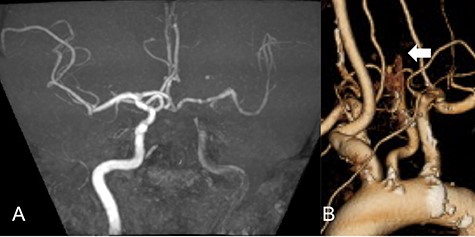

We performed CAS and started dual antiplatelet therapy 27 days after stroke onset to prevent further dissection and cerebral infarction recurrence. The dissection started 1.5-cm below the carotid bifurcation (Fig. 3A). An 8 fr guiding catheter (FlowGate2 Balloon Guide Catheter, Stryker, Fremont, CA, USA) was positioned at the proximal portion of the left CCA with a micro-guidewire (ASAHI CHIKAI Black, Asahi-Intecc, Nagoya, Aichi, Japan) crossing the dissected lesion. A distal protection device (SpiderFx Embolic Protection Device, Medtronic, Minneapolis, MN, USA) was deployed at the petrous portion of the ICA. IVUS was first advanced into the petrous ICA, and vessel wall imaging was performed by slowly withdrawing the device. IVUS imaging confirmed the existence of the dissection’s pseudo-lumen starting 1-cm proximal to the carotid bifurcation (Fig. 3C). IVUS provided the ICA and CCA diameters, which helped decide the most suitable stent (Fig. 3B and C). To adequately cover the dissection lesion, we placed two opened cell stents (Protégé, Medtronic, Minneapolis, MN, USA); one was an 8–6-mm tapered model with a length of 40 mm to cover the lesion from the distal CCA end to the proximal portion of ICA. Another was a 10-mm straight model with a length of 40 mm covering the CCA. Post-dilation was performed SterlingTM Balloon Dilation Catheter (Boston Scientific, Natick, MA, USA) with 5 × 20 mm covering both stents’ edges. The final angiography showed successful treatment with a smooth intra-arterial lumen (Fig. 4A). IVUS imaging showed sufficient stent coverage of the entire dissection lesion. It also confirmed a good expansion of the stent to the dissection area’s arterial wall with no plaque protruding the stents (Fig. 4B).

Angiography after stent placement showed favorable patency of the carotid artery with a smooth intra-arterial lumen (A). IVUS performed after stenting confirmed an excellent expansion of the stent to the dissection lesion’s arterial wall with no plaque protruding the stents (B).